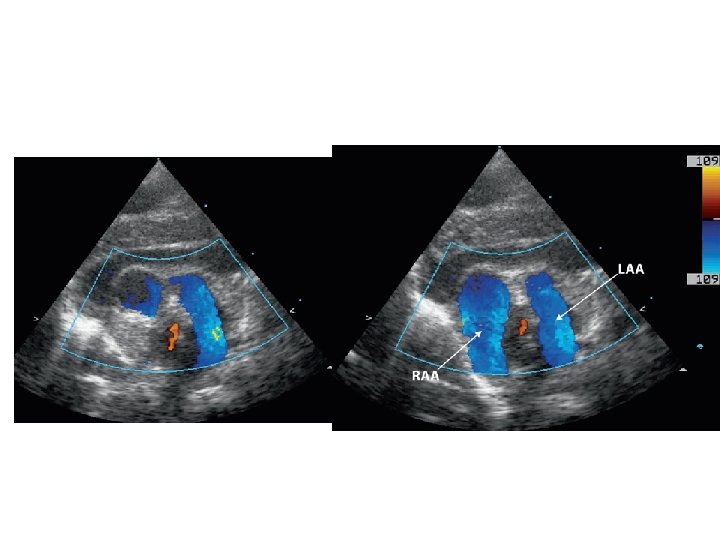

Cervical aortic arch

Cervical arch-different types